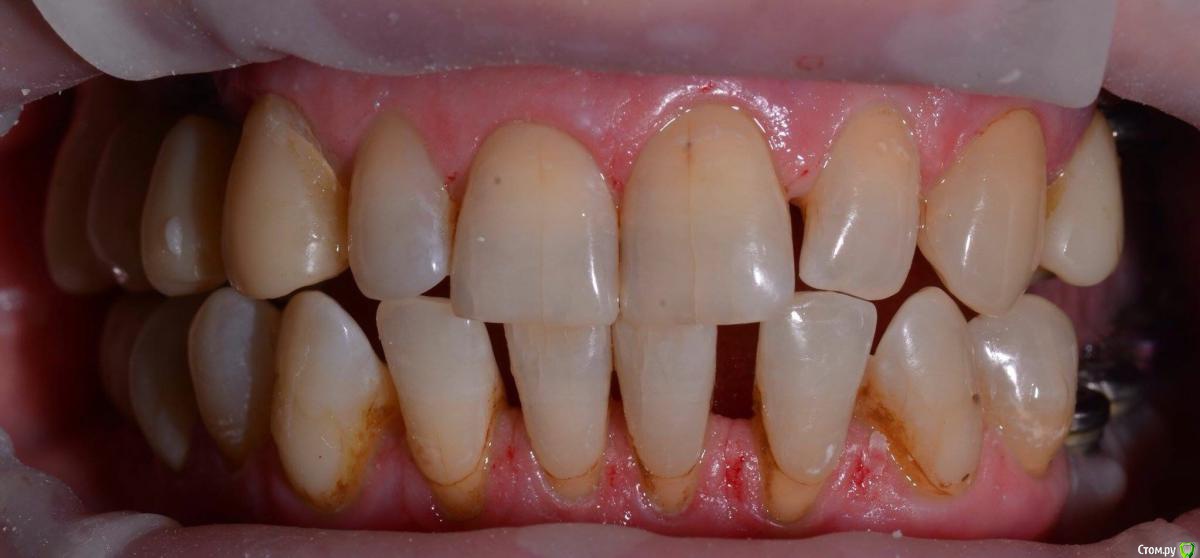

togrul Опубликовано 4 апреля, 2016 Поделиться Опубликовано 4 апреля, 2016 Добрый вечер коллеги. Восстановили зубы безметалловыми коронками Емах зубы и Циркон наслоением на имплантатах. 9 Ссылка на комментарий

chervoncevdaniil Опубликовано 5 апреля, 2016 Поделиться Опубликовано 5 апреля, 2016 Обсуждали с пациентом что цвет шеек будет отличаться от блич коронок?Не был против? Ссылка на комментарий

togrul Опубликовано 5 апреля, 2016 Автор Поделиться Опубликовано 5 апреля, 2016 Конечно . Оставил для хорошей гигиены. Так как от хирургии отказалась. Ссылка на комментарий

Art 7 Опубликовано 5 апреля, 2016 Поделиться Опубликовано 5 апреля, 2016 Тогрул привет, так не оставляй, надо такие вещи либо закрывать десной либо керамикой. Керамика гигиеничнее чем оголеный корень 1 Ссылка на комментарий

togrul Опубликовано 5 апреля, 2016 Автор Поделиться Опубликовано 5 апреля, 2016 Тогрул привет, так не оставляй, надо такие вещи либо закрывать десной либо керамикой. Керамика гигиеничнее чем оголеный кореньПривет Артур. Посоветовавшис с пародонтологом решили оставить на границе ЭЦГ. И с точки зрения адгезивный фикцисации цемент зуба как я понимаю тяжело адгезивно подготовить. Спасибо . Ссылка на комментарий